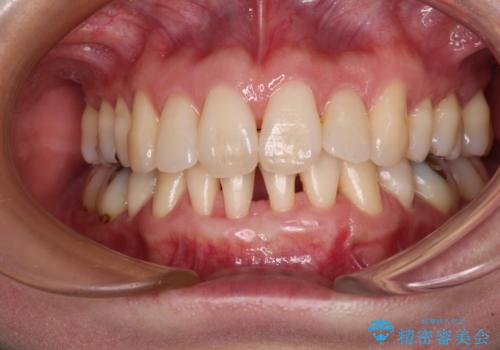

下顎前歯の歯肉退縮 歯肉移植による根面被覆

- 矯正治療により下の前歯の歯肉が退縮してしまい、根が見えていることが気になるとのことで来院された患者様です。

歯と歯と歯肉の間にある三角形の隙間(ブラックトライアングル)は歯肉移植では改善できないため、根面被覆できる量に限界がありましたが、最大限回復させることができました。